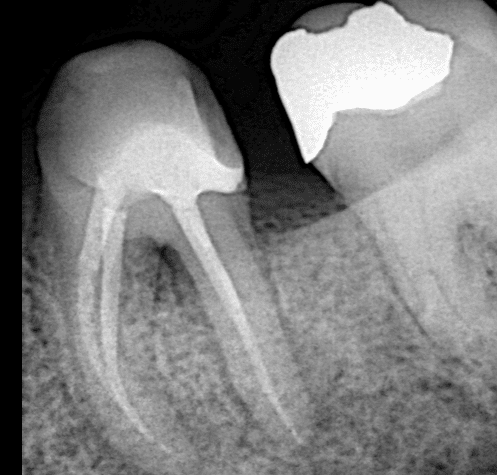

Final x-ray showing the fitness of the overlay